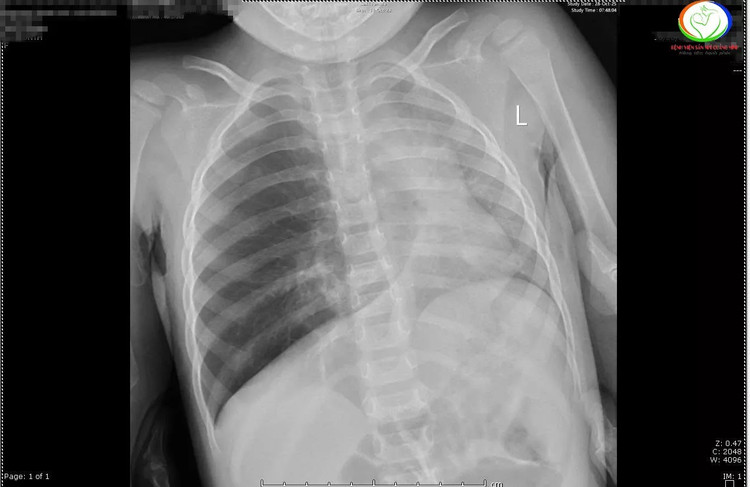

Qua phim chụp X –quang cho thấy các trẻ có hình ảnh ứ khí, mờ quanh rốn phổi. Riêng bệnh nhi N.N.L phổi trái giảm thể tích, kém sáng, xẹp phổi dạng dài thùy dưới phổi phải. Các bác sĩ đã hội chẩn khẩn cấp và chỉ định nội soi khí thanh phế quản cấp cứu gắp dị vật cho trẻ.